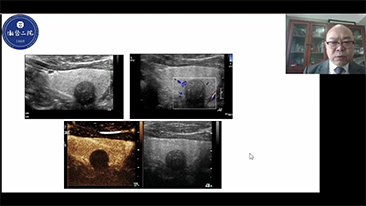

Wie deutlich k?nnen Sie eine Leber erkennen?

Bei fokalen Leberl?sionen wie H?mangiomen oder Leberkrebs spielt die Ultraschallkontrastdarstellung eine zentrale Rolle. Mit der weitreichenden nichtlinearen UWN+Kontrast-Bildgebungstechnologie k?nnen eine bessere Penetration, ein h?heres Kontrast-Gewebe-Verh?ltnis, eine geringere MI und eine l?ngere Beobachtung der Durchblutungsdauer erreicht werden.